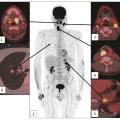

Cancers des voies aérodigestives supérieures : le cas particulier du cancer du nasopharynx

Les carcinomes nasopharyngés (CNP), ou cancers du cavum, sont le plus souvent diagnostiqués devant des signes rhinologiques, auditifs ou neurologiques non spécifiques, conséquences de leur évolution locorégionale ; plus rarement, des signes généraux doivent faire évoquer ce diagnostic, particulièrement si le patient est natif de la…